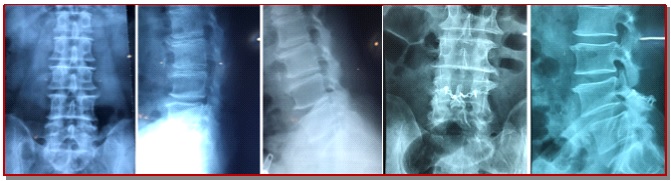

The aim of our study is to evaluate the clinical and functional outcome following lumbar laminoplasty with posterior element reconstruction with mini-plate and screws for multilevel lumbar canal stenosis. This study was done on 40 patients (18 males and 22 females) of degenerative multilevel lumber canal stenosis patients underwent open double door lumbar laminoplasty with posterior element reconstruction with mini-plate and screws from January 2015 to June 2018. Thirty four patients underwent surgery for 2 level involvement and 6 underwent for 3 level involvement of lumbar canal stenosis. The mean post-operative hospital stay was 5.2 ± 1.1 days. Per-operative complication was dural tear in 2 cases. Pre-operative mean VAS score of back pain and leg pain were 7.0 ± 0.7 and 7.2 ± 1.1 which were significantly reduced to 1.0 ± 0.2 and 1.0 ± 0.8 respectively at final follow-up. All patients were followed-up for minimum 1 year. Pre-operative mean Japanese Orthopedic Association score was 8.6 ± 2.2 which was significantly increased to 14.8 ± 0.4 after 12 months of surgery. Pre-operative mean Oswestry Disability Index was 34.4 ± 3.0 which was significantly reduced to 8.5 ± 2.2 after 12 months of surgery. The outcome of lumbar laminoplasty with posterior element reconstruction with mini-plate and screws for multilevel lumbar canal stenosis show good result and can be one of the good option for the treatment for multilevel lumbar canal stenosis.